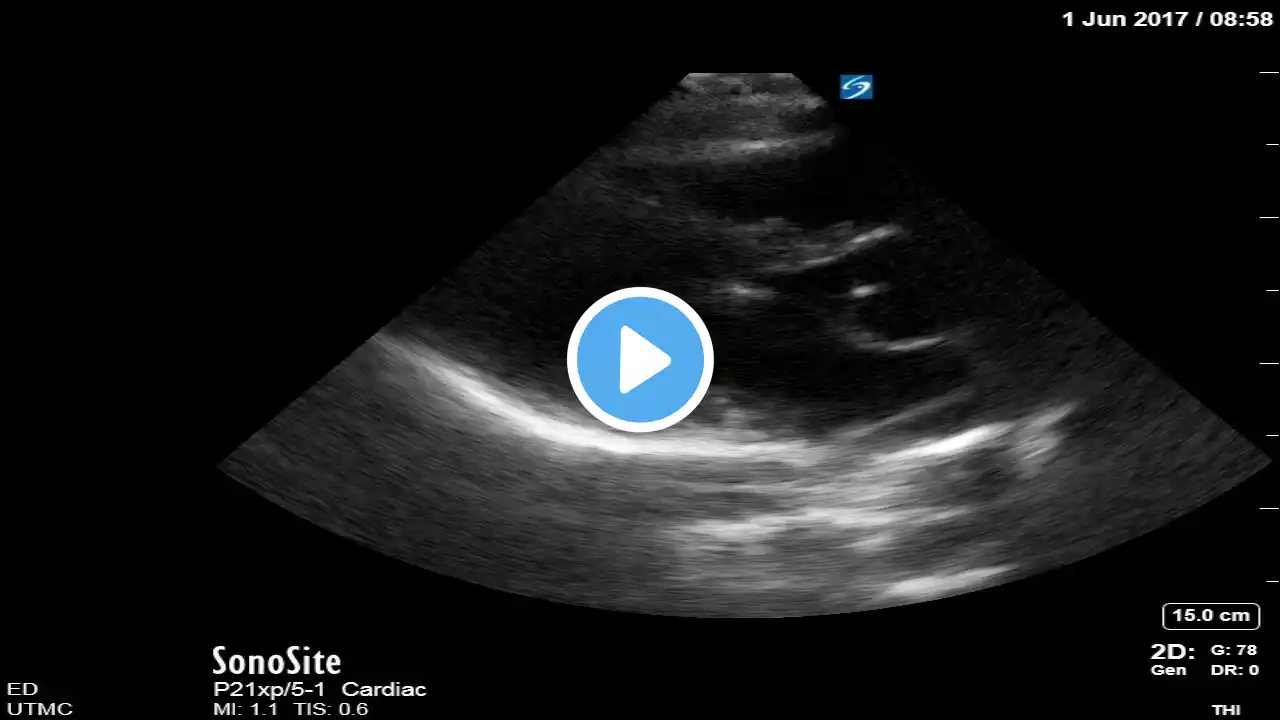

full [fat] IVC mildly collapsing in case of cardiogenic shock

you can see in our channel playlist all varieties of IVC in different types of shock